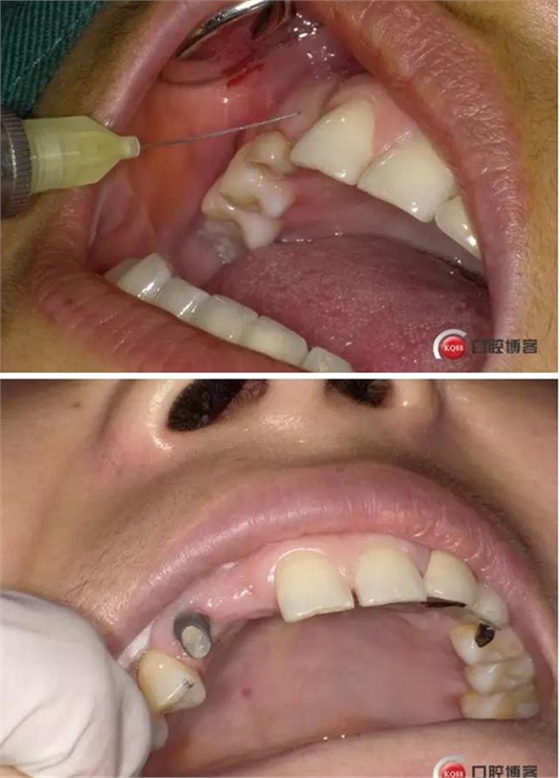

患者右上二缺失,CT示唇腭向骨量不足,右上3為乳牙滯留且骨量足設(shè)計(jì)右上三即拔即種手術(shù)